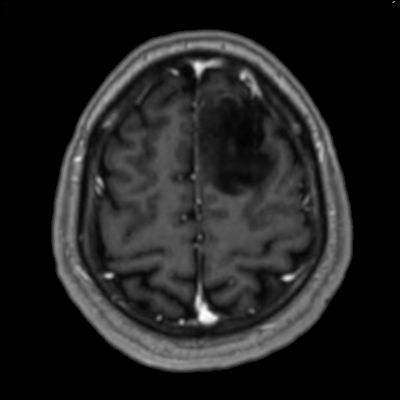

- Sol frontal kortikal-subkortikal yerleşimli aksiyel T2A görüntüde hiperintens sinyal özelliği gösteren (oklar) ve FLAIR görüntüde sinyali ağırlıklı olarak baskılanan (oklar) kitlesel lezyon izleniyor. Lezyon T1A görüntüde hipointens olup post-kontrast T1A görüntüde bu düzeyde patolojik kontrastlanma izlenmiyor (oklar).

- FLAIR’de T2’ye benzer şekilde hiperintens görünür. Ancak T2–FLAIR mismatch bulgusu, bu tümör tipi için oldukça karakteristiktir.

- T2–FLAIR mismatch bulgusu, T2AG’de homojen hiperintensite ile FLAIR görüntüde santral sinyal baskılanmasının ve çevrede hiperintens halka görünümünün bulunduğu bir fenomendir. Bu bulgu, özellikle IDH-mutant, 1p/19q kodelesyonu olmayan astrositomları tanımlamada oldukça özgül bir biomarker olarak literatürde vurgulanmıştır. Ayırıcı tanıda akla gelmesi gereken oligodendrogliomlarda T2/FLAIR mismatch bulgusu genellikle görülmez.

- Olgumuzda T2-FLAIR mismatch bulgusu mevcut olup, opere edilmiş ve tanısı histopatolojik olarak konulmuştur.